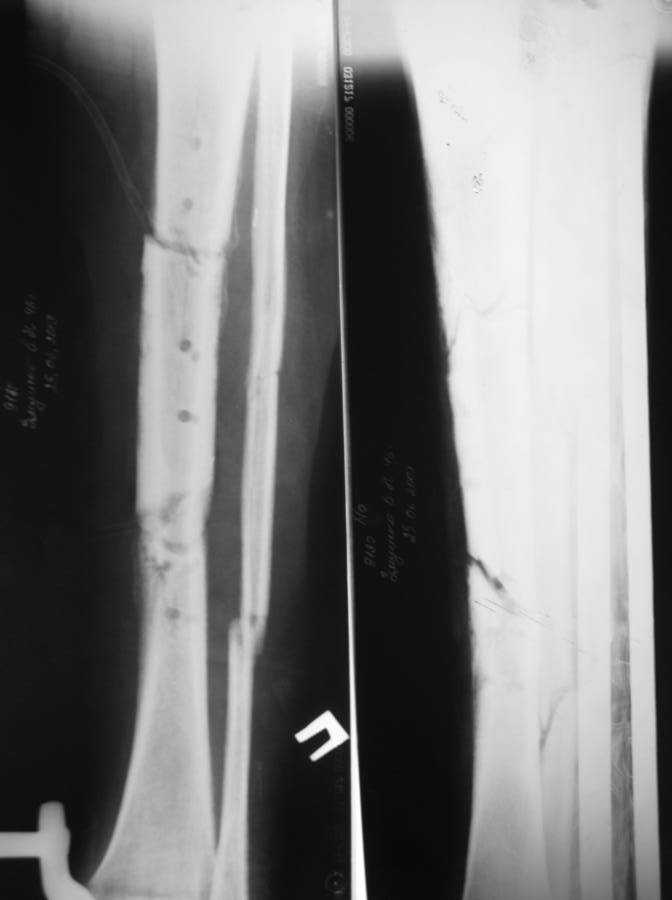

Недавно оперирован повторно- малоберцовая кость пересечена на уровне верхнего и нижнего отрезков  большеберцовой кости, перемещена на область дефекта большеберцовой кости, фиксирована в аппарате. Рентгенснимки и фото голени больного прилагаю.<br>

Послеоперационный период протекал без осложнений, раны зажили, швы сняты, больной ходит с полной опорой на ногу в аппарате, воспаления мягких тканей вокруг спиц нет. Планируется постепенное увеличение нагрузки на перемещённую малоберцовую кость путём этапного удаления спиц под рентген контролем. <br>

Имя     : рентген после операции.jpg

Тип     : image/jpeg

Размер  : 46551 байтов

Описание: отсутствует

Url     : http://weborto.net:8080/pipermail/ortho/attachments/20090926/a941c8f6/attachment-0012.jpg